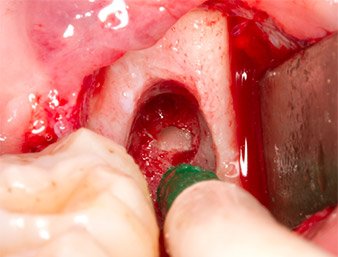

A continuación, se utilizó el accesorio P1 para retirar de una pieza el resto radicular de aproximadamente seis milímetros de longitud (figura 11).

El tejido inflamatorio periapical se retiró también con sumo cuidado utilizando un excavador manual. La figura 12 muestra el alvéolo vacío con el nervio alveolar inferior expuesto.

radicular extraído

Imagen 11: El resto radicular extraído medía más de 6 milímetros.

Nervus alveolaris inferior

Imagen 12: En la profundidad del alvéolo se distingue el nervio alveolar inferior.